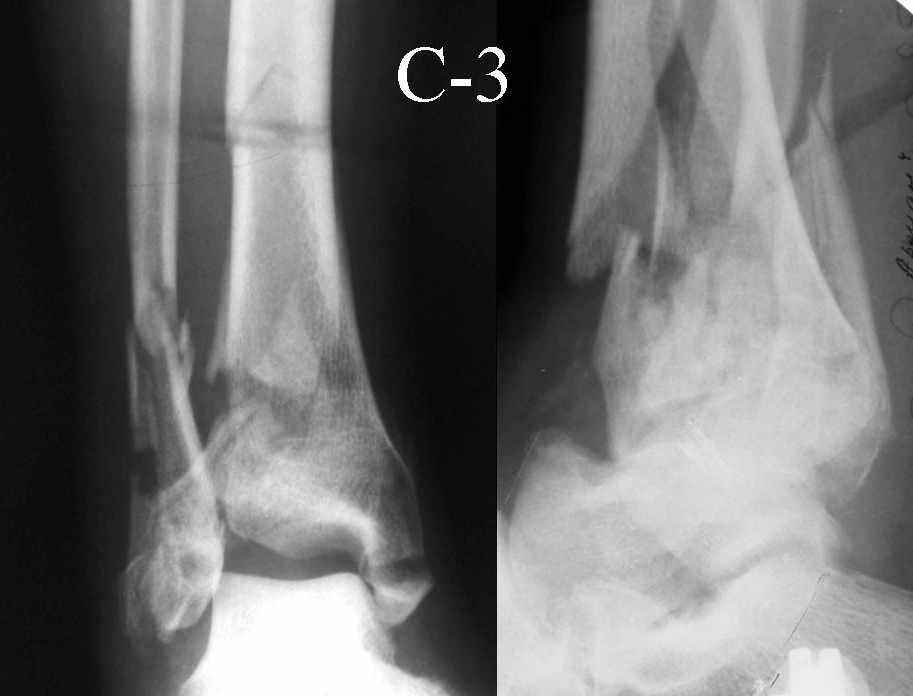

Это типичный перелом пилона, который надп лечить только открыто.Извини те что опоздал к обсуждению, но даже если вы уже оперировали больного по Илизарову это даже лучше.Посылаю картинки.